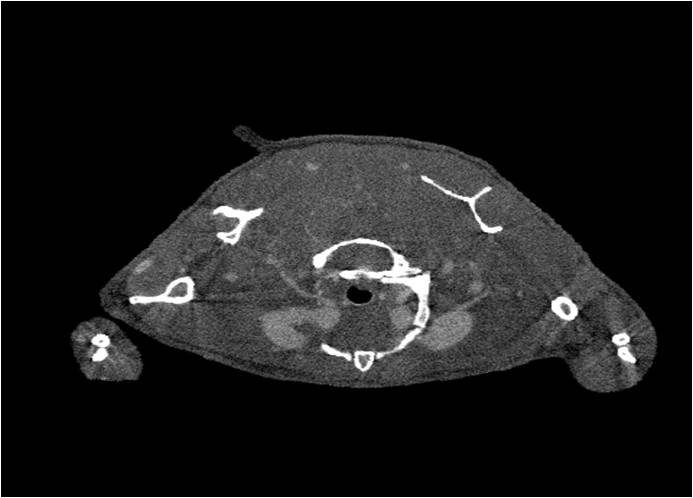

腫瘤血管生成

肺轉(zhuǎn)移

小鼠模式,22.5μm像素

正常

8天 14天

無造影劑注入 造影劑注入